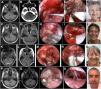

ResultadosSe estudiaron 40 pacientes con edad promedio de 49,4 años y proporción masculino/femenino de 0,4:1. De ellos, 31 presentaron schwanomas vestibulares (77,5%), cinco meningiomas (12,5%), dos colesteatomas (5,0%) y dos metástasis (5,0%). Predominaron los schwanomas vestibulares tipo Hannover IIIb, IVa y IVb. La resección fue total o casi total en el 92,5% de los pacientes. Se conservó la audición en el 62,5% de los pacientes y el 80% presentó función aceptable del nervio facial a los seis meses. La estadía hospitalaria promedio fue de 7,5 días. Se observó un elevado porcentaje de resección total o casi total y de recuperación funcional. La frecuencia de complicaciones fue baja.

ResultsA number of 40 patients were included. The age average was 49.4 years and male/female proportion was 0.4-1. We found 31 vestibular schwannomas (77.5%), five meningiomas (12,5%), two cholesteatomas (5,0%) and two metastases (5.0%). Vestibular schwannomas Hannover type IIIb, IVa and IVb predominated. The surgical resection was total or near-total 92.5% of patients. Hearing preservation rate was 62.5% and acceptable facial function nerve function rate was 80% after six months. Hospital stay was 7.5 days. The total or near total resection and functionally preservation rate was high. Complications were unusual.